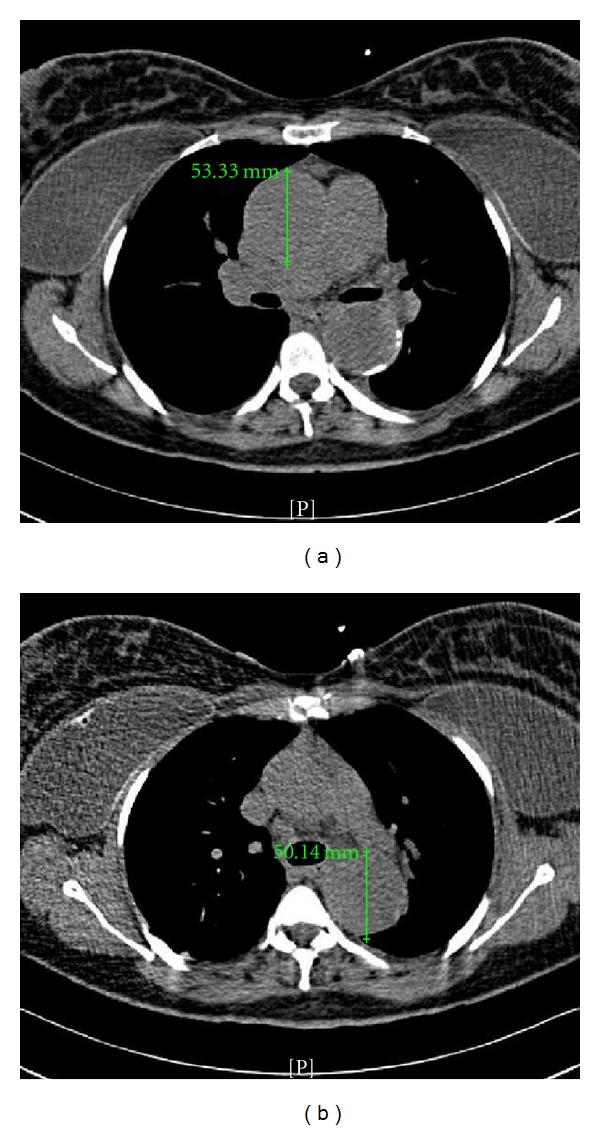

Preexisting aortic disease can worsen during pregnancy as physiologic hemodynamic changes evolve. At a large academic institution, a patient with a remote history of vasculitis presented with a second trimester pregnancy with increasing aortic dilatation and aortic insufficiency. Extensive obstetric discussions encompassed maternal cardiac risks from continuing the pregnancy and fetal risks from maternal cardiac intervention. This patient desired termination of pregnancy to avoid further complications and to expedite surgical aortic repair.

随着生理血流动力学变化的发展,孕前存在的主动脉疾病在孕期可能会恶化。在一家大型学术机构,一名有血管炎既往史的患者在孕中期就诊,出现主动脉扩张和主动脉瓣关闭不全加重。广泛的产科讨论涵盖了继续妊娠的母体心脏风险以及母体心脏干预的胎儿风险。该患者希望终止妊娠以避免进一步并发症并加快主动脉手术修复。